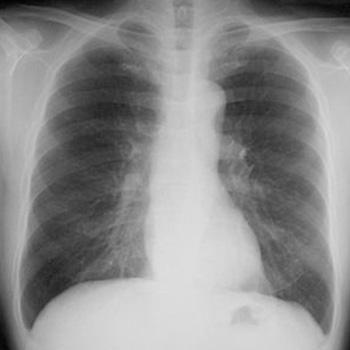

病院でレントゲン写真やCTを撮ってもらうのは「外部被ばく」です。

医療の分野では、放射線を使用した検査として、レントゲン検査・胃バリウム検査・CT検査・マンモグラフィ検査などがあります。